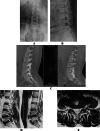

Figures